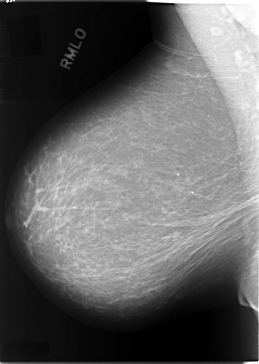

Digital Database for Screening Mammography

Volume: cancer_09 Case: C-0084-1

C_0084_1.RIGHT_MLO

RIGHT_MLO LINES 5824 PIXELS_PER_LINE 4136 BITS_PER_PIXEL 12 RESOLUTION 50 NON_OVERLAY